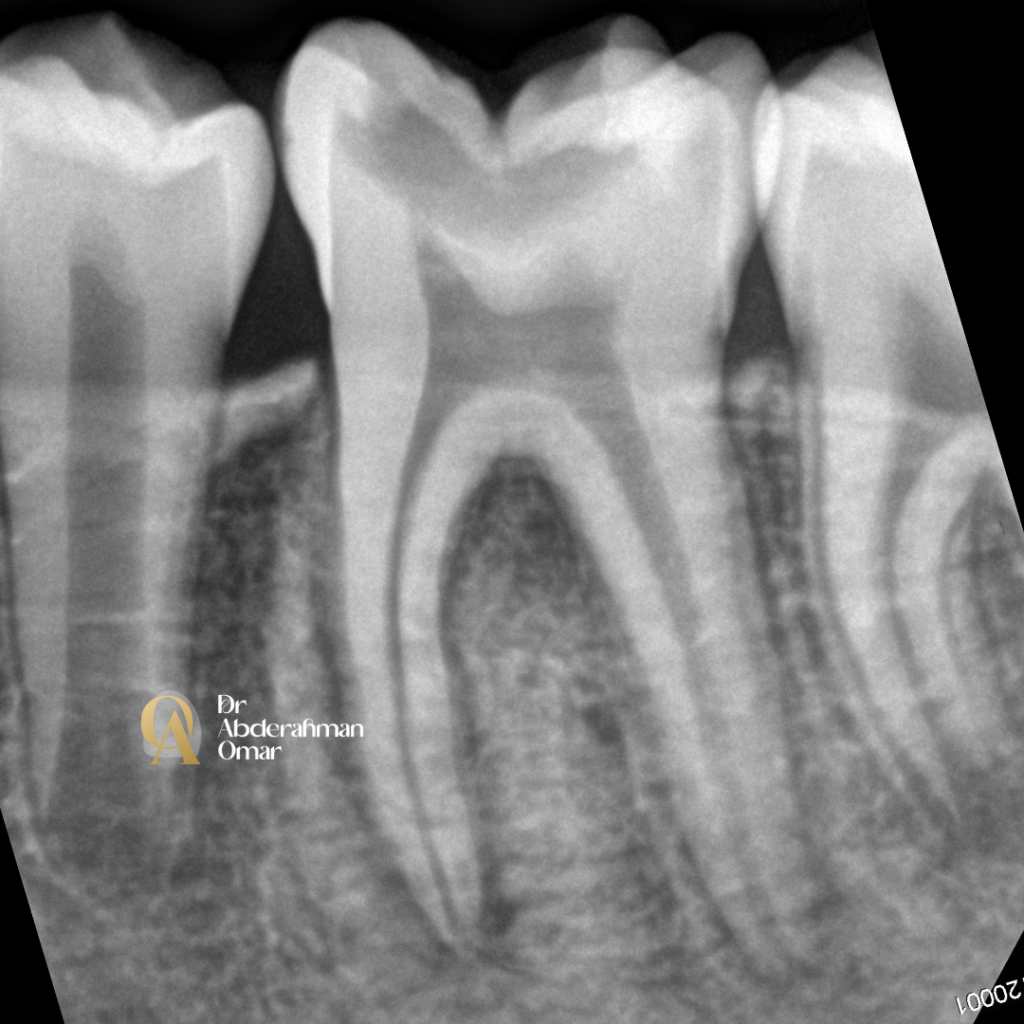

• Obturation using cold lateral compaction technique with gutta-percha and bioceramic sealer

Post-operative radiograph confirmed optimal length, fill density, and canal obturation in all five canals.